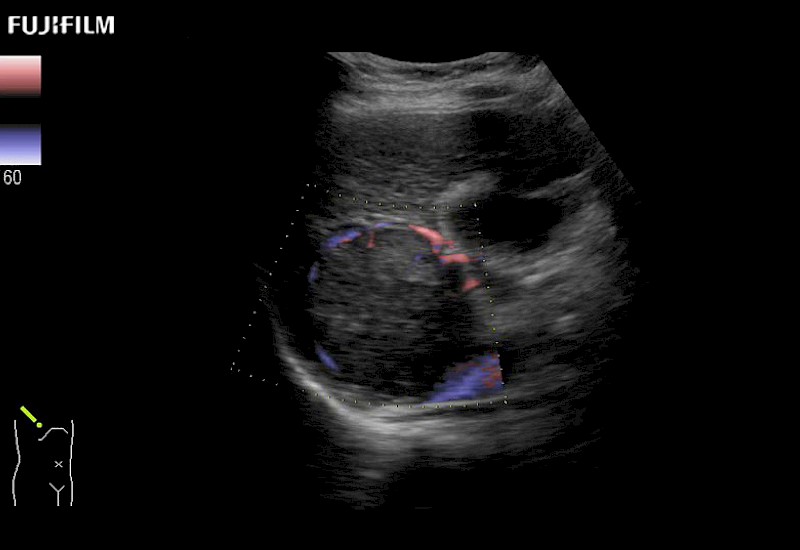

Learn moreFujifilm Healthcare continues to listen to the experts, our neurosurgeons, by developing an ultrasound system specifically designed for the Operating Room.

Guidance is the fundamental purpose for all of our surgical ultrasound technology. Fujifilm Healthcare is committed to designing tools that help neurosurgeons navigate inside the human body and provide the necessary information to immediately make critical surgical decisions.

With the ARIETTA Precision the next level of surgical ultrasound is here.